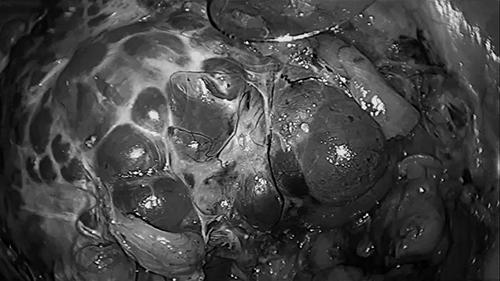

腹腔镜多囊肾手术中图像